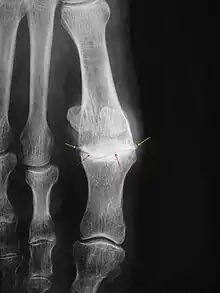

Des radiographies doivent être pratiquées qui, seules, permettent d'affirmer le diagnostic en identifiant les signes habituels d'arthrose : pincement articulaire, ostéophytes, géodes, condensation. Elles doivent également mesurer l'axe du premier rayon pour quantifier l'éventuelle déformation associée (hallux rigido-valgus).